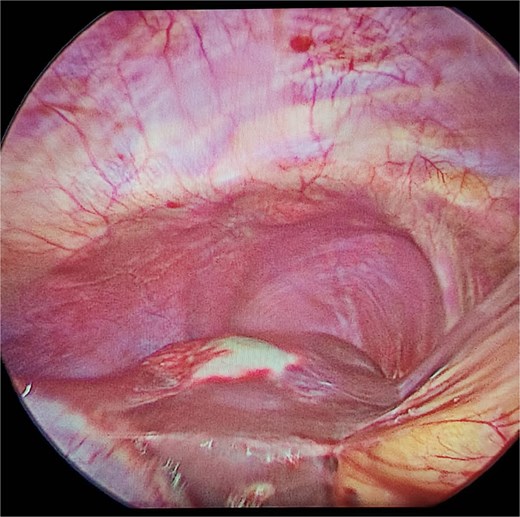

The treatment of cystic hydatid disease includes percutaneous drainage, medical therapy, and surgical intervention. While percutaneous aspiration-injection-reaspiration and albendazole therapy are viable options, surgery remains the preferred treatment for complicated cysts, offering the potential for complete cyst removal and full recovery [3, 6]. In our case, laparoscopic pericystectomy was successfully performed, leading to a favorable postoperative outcome (Figs 2–4).

Laparoscopic view of hepatic hydatid lesion (white focus on the liver surface).